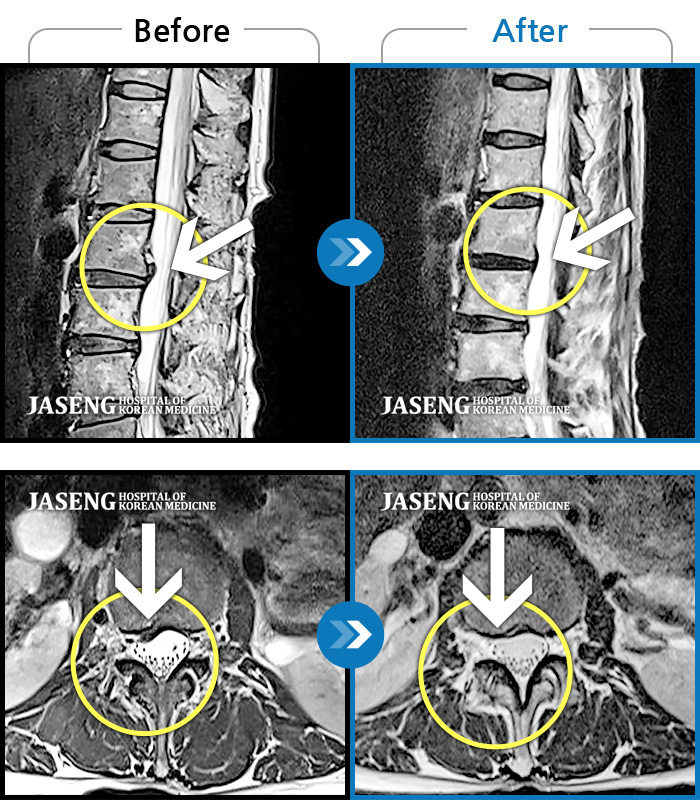

MRI 치료사례

우측 골반으로 지속적인 통증이 있고 어떤 자세를 취해도 아프다.